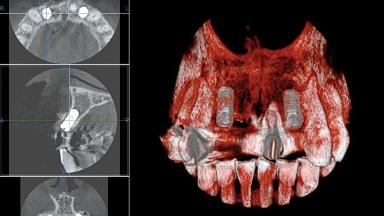

Replacement of Four Incisors with a Fixed Dental Prosthesis on Two Bone-Level Implants

In November 2007, a 52-year-old woman presented with a failing restoration of the anterior maxilla in the form of a four-unit metal-ceramic fixed partial denture. As secondary caries had led to fracture of the abutment teeth bilaterally, the existing restoration could not be preserved. The patient was in good systemic health, and her medical history was without significant findings. Nor did the ensuing intra- and extraoral examination yield any significant findings. The patient had both a high lip line and high esthetic expectations. The preextraction findings suggested that no hard-tissue augmentation would be required before implant placement. After discussing the higher risk of immediate placement with the patient, she agreed to undergo “early implant placement after soft-tissue healing” simultaneously with guided bone regeneration (GBR) for hard-tissue augmentation.